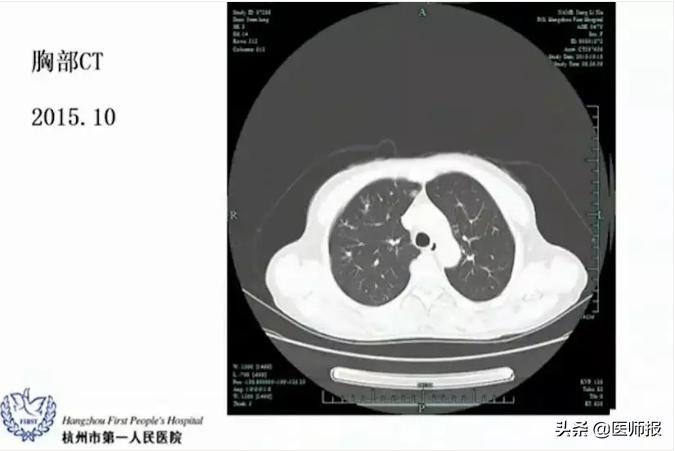

两次胸部CT的结果还是不太一样的,8月份的片子主要集中在右上叶的后段和右下叶的背段,10月份的片子显示明显的病变比原来增加了。